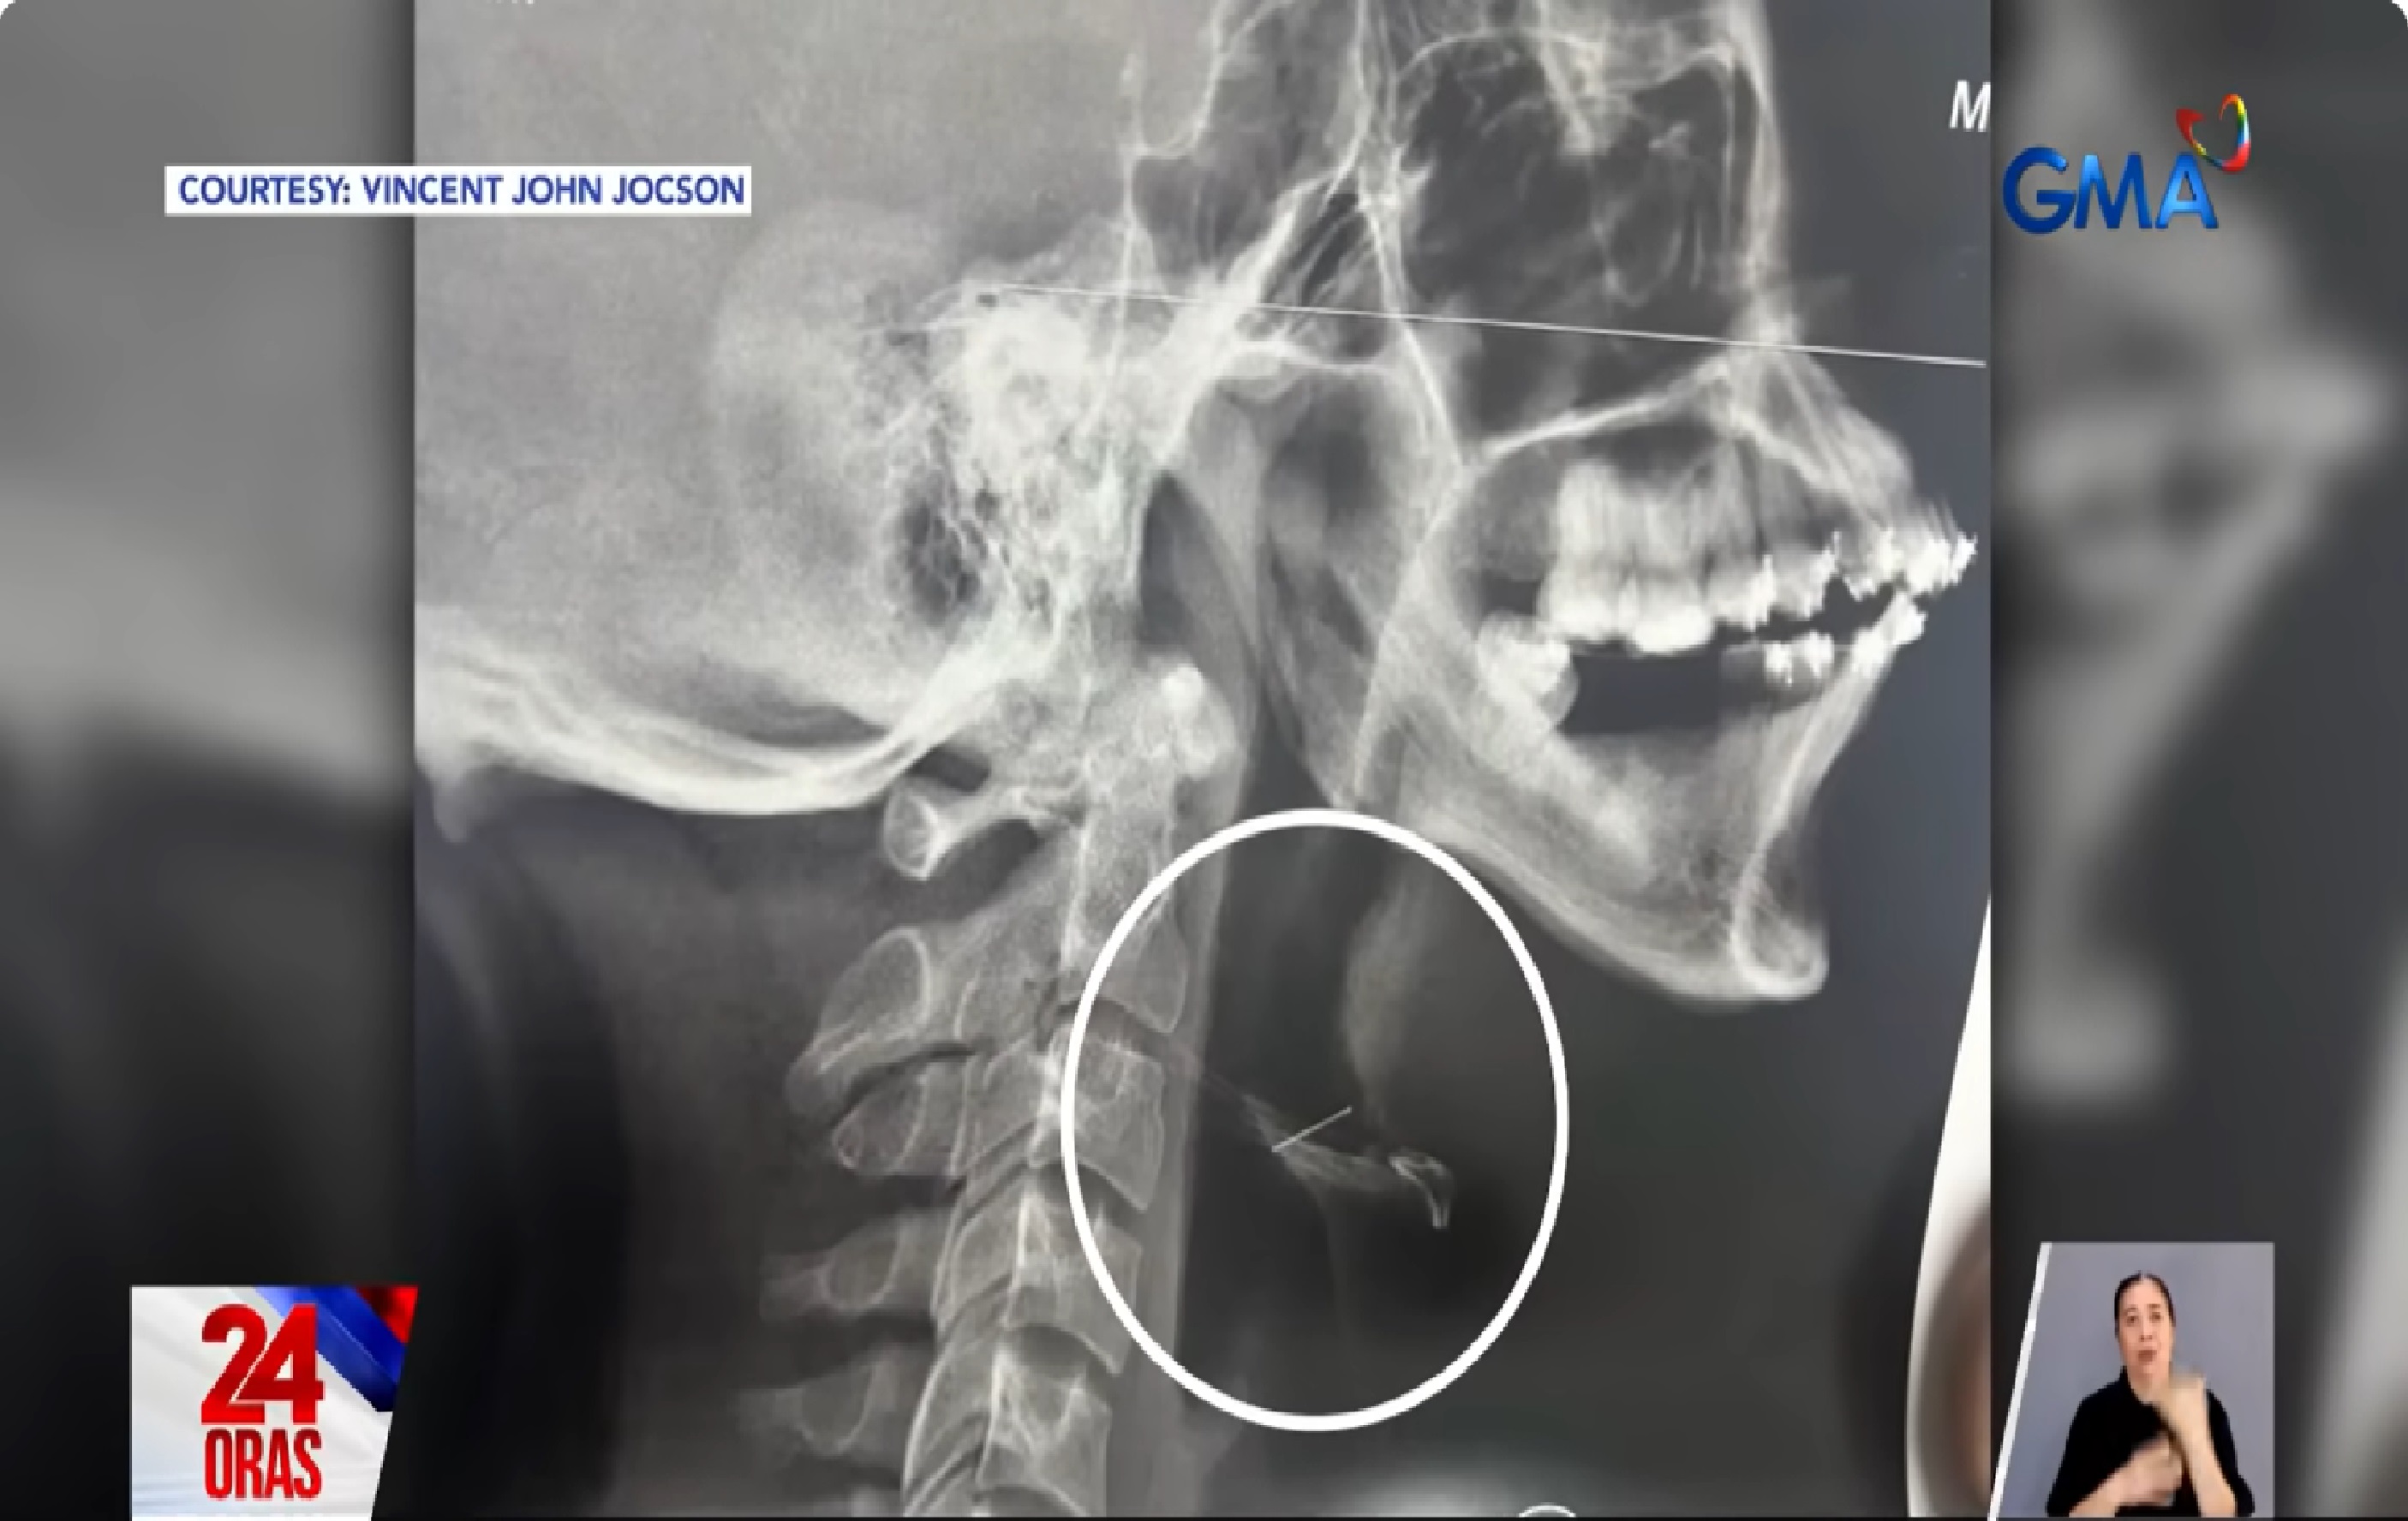

Ayon kay Adan, nang mangyari ang kagatan, sinabunutan at hinubaran siya ni Eva at kinagat ang kaniyang ari.